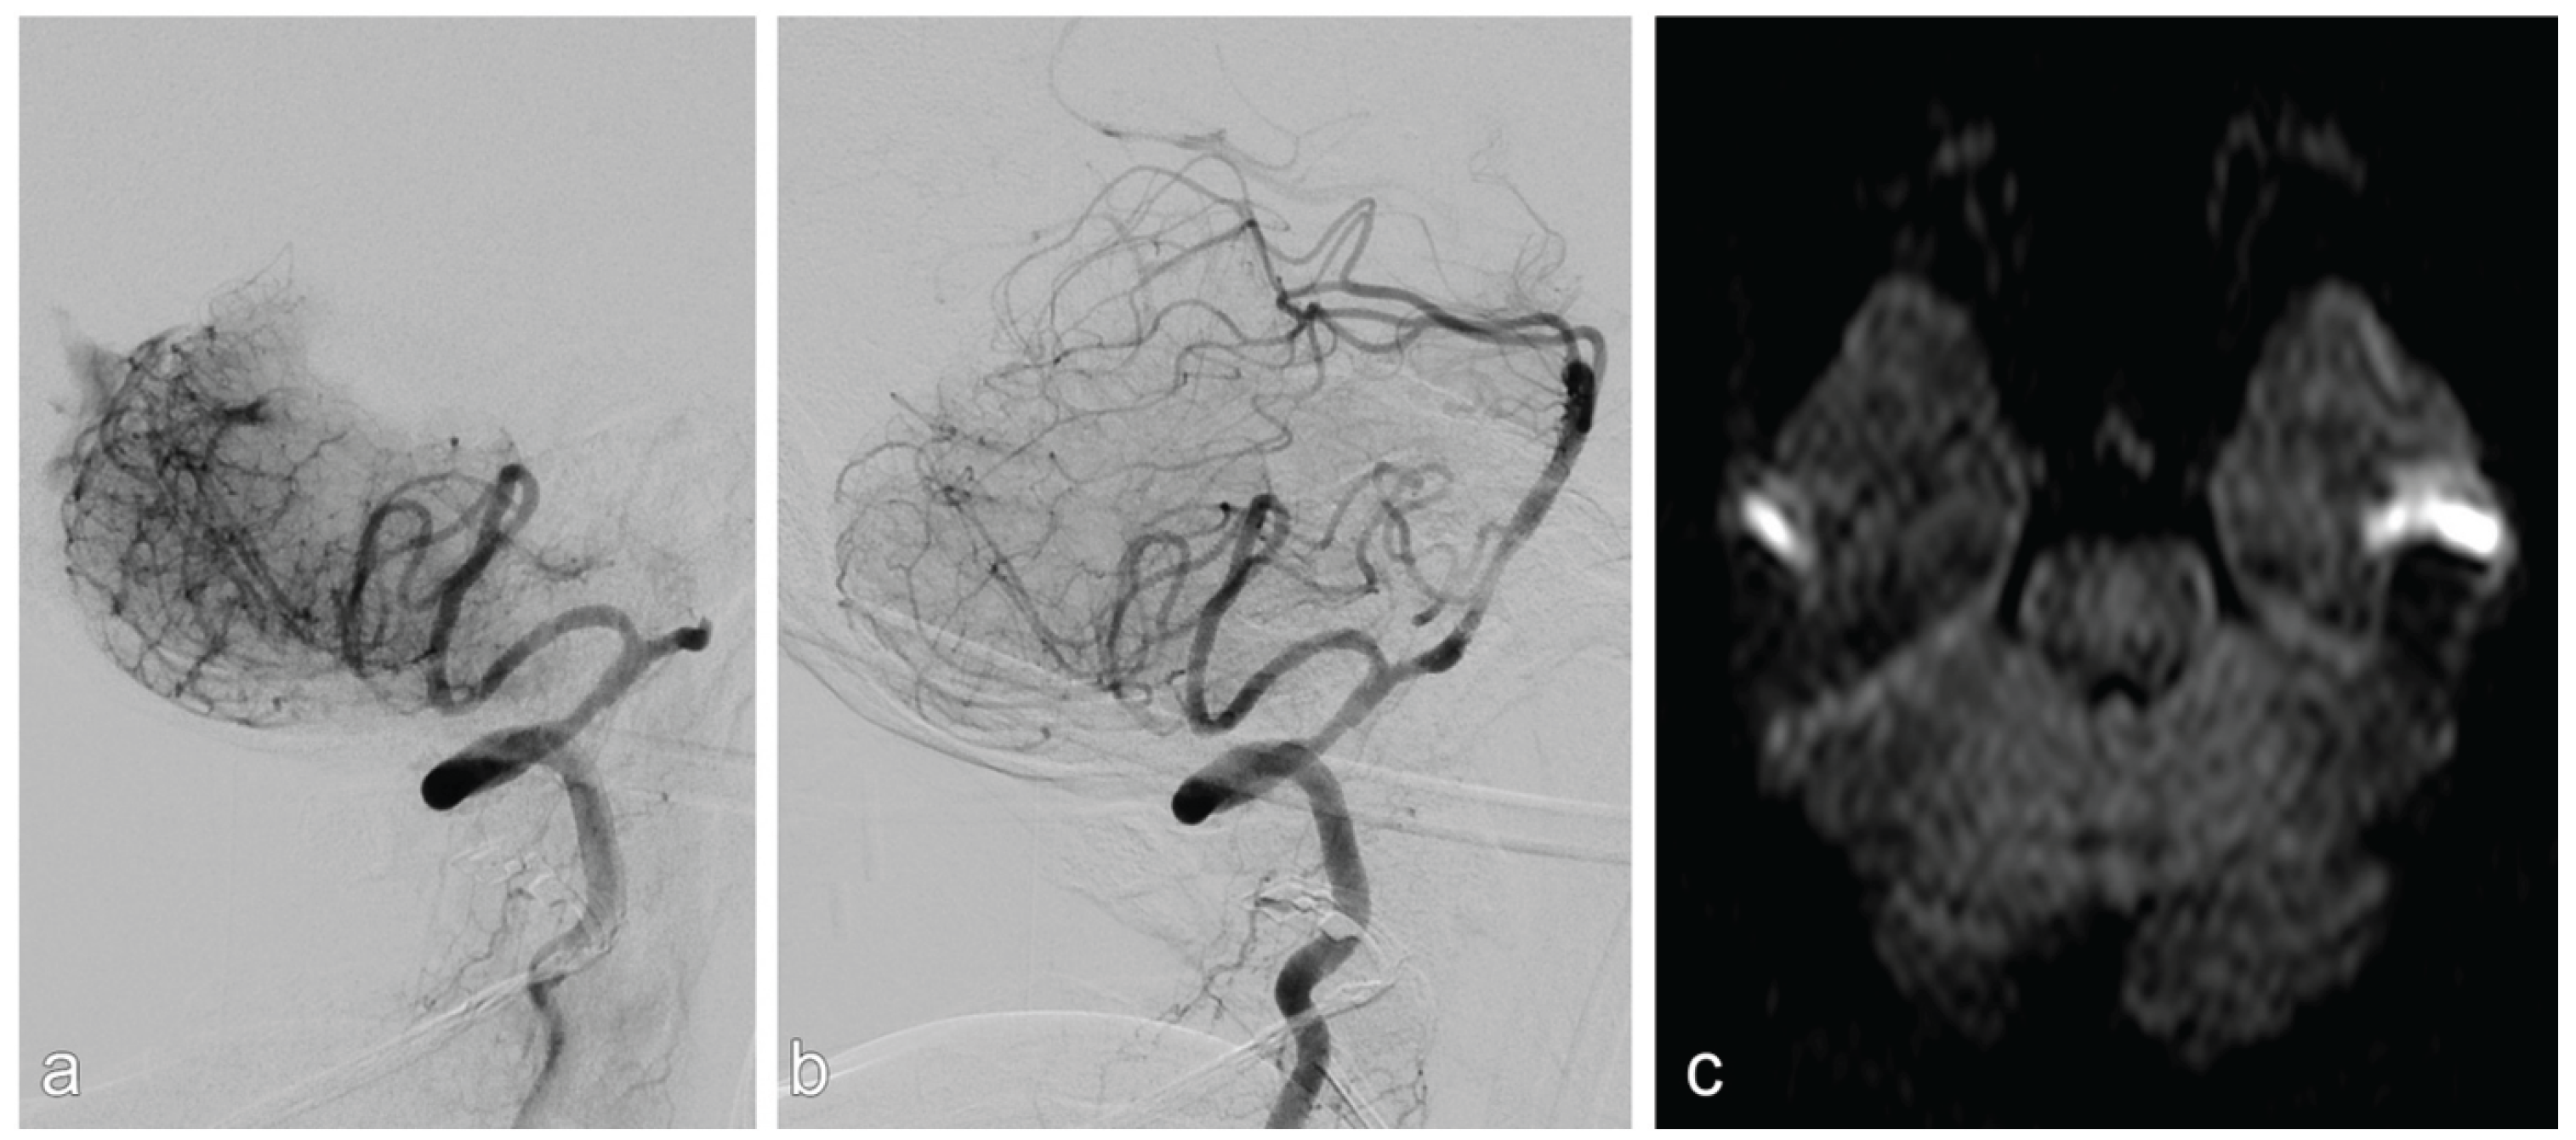

- Intracranial dissections with compromised side branch patency occurred in two out of 32 patients. Both cases were in the vertebrobasilar circulation and occurred after balloon angioplasty. In one of these two cases, there was subsequent in-stent thrombosis, which was fatal. In the other case, there were embolic and perforator infarction which led to worsening of the neurologic symptoms.

- Acute and subacute stent thrombosis were observed in two cases, both of which occurred in the vertebrobasilar circulation and were symptomatic: one of these two patients had progressive infarction, which led to neurological worsening (mRS=5); the other had stent-thrombosis after dissection, which was fatal (mentioned previously).

Outcome Parameters in Non-ELVO Group